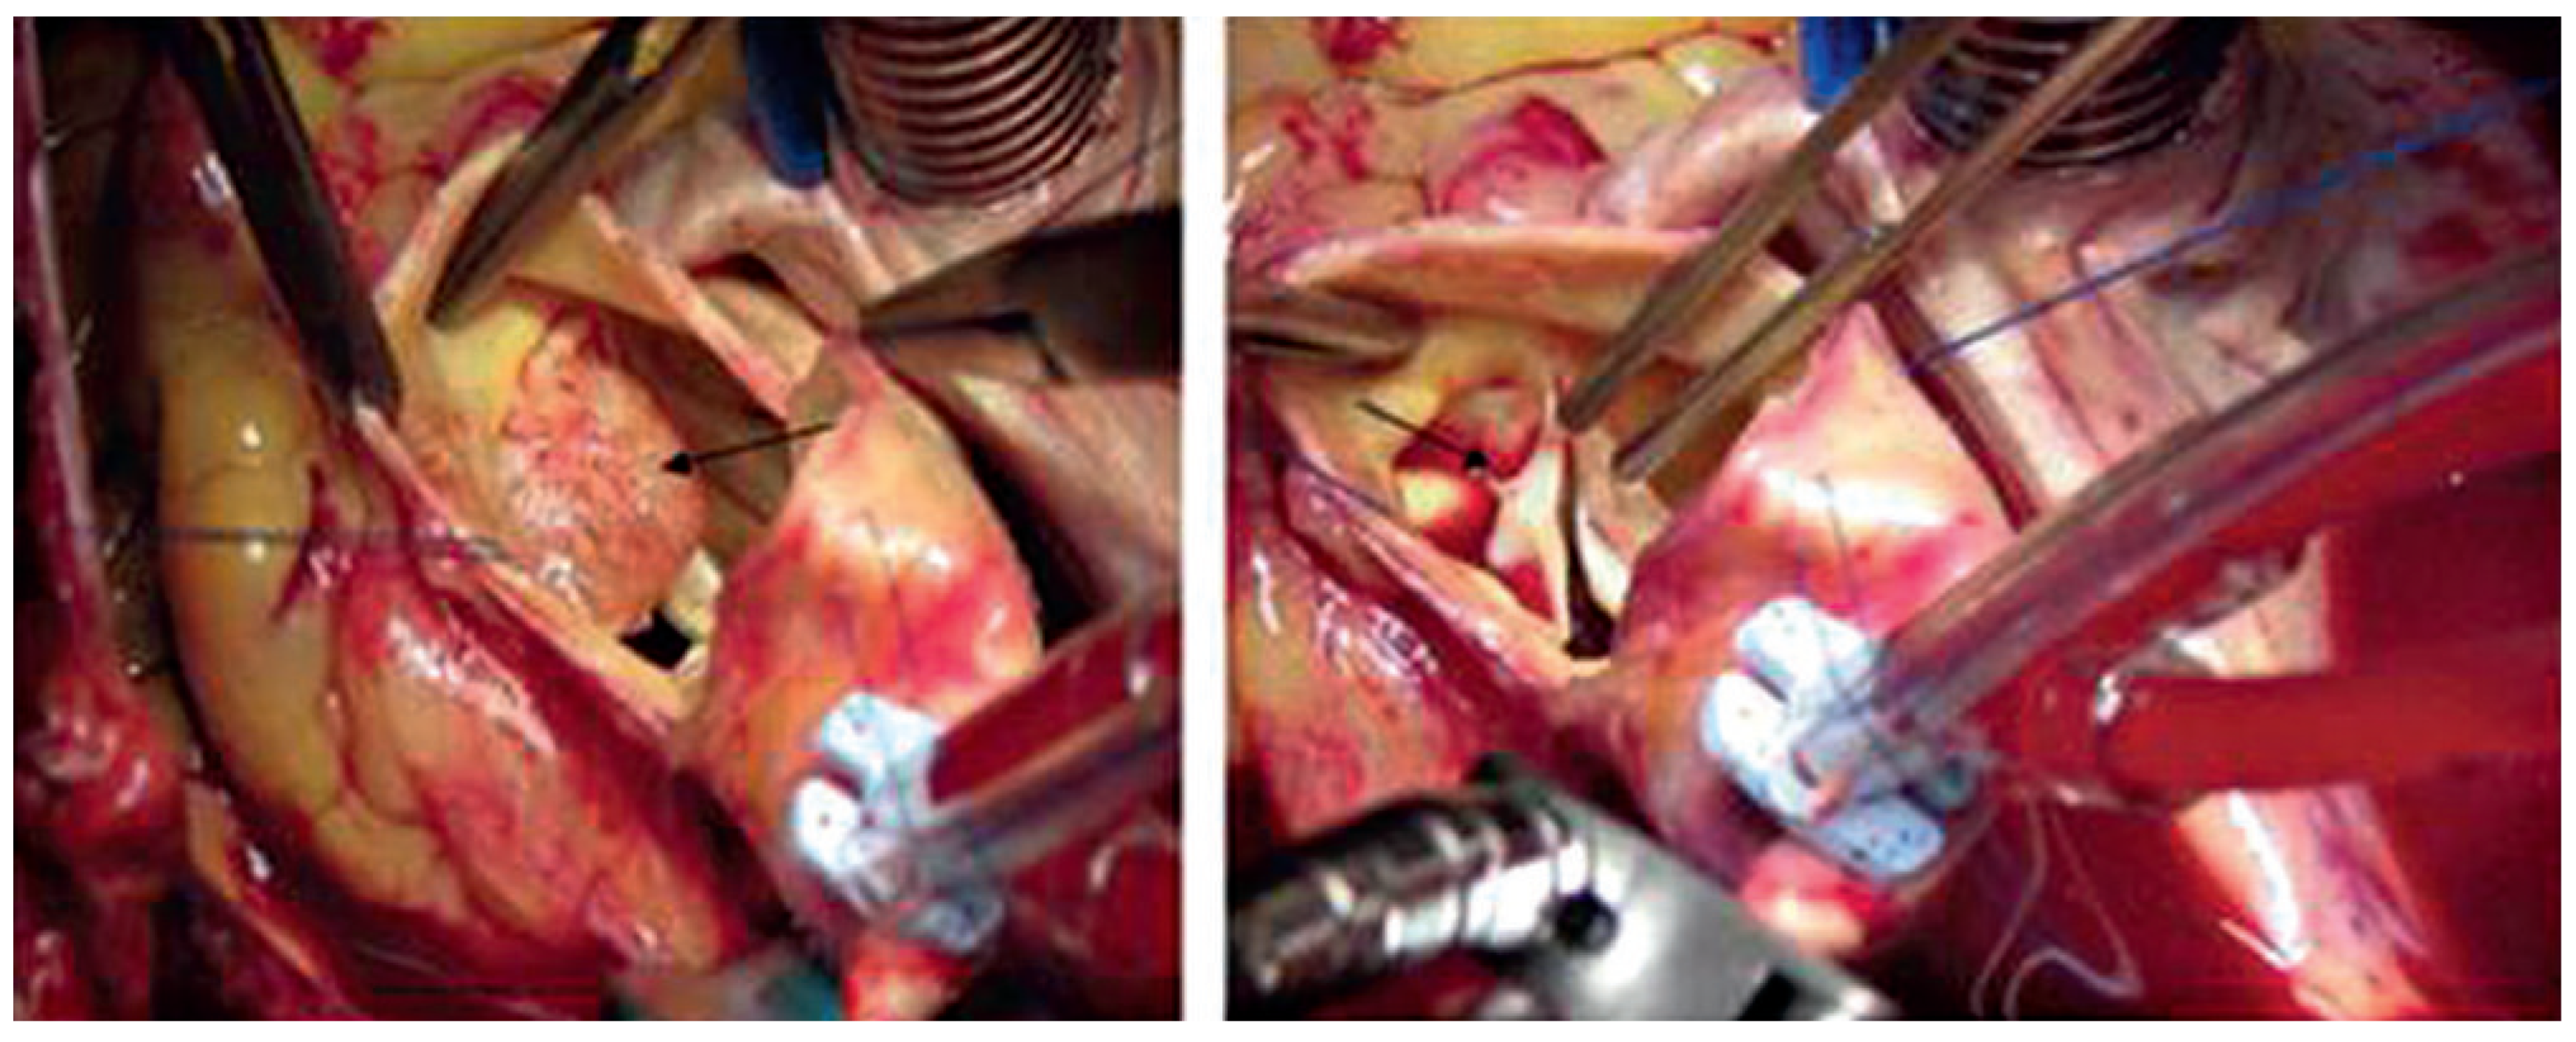

Case report 5: Poorly differentiated angiosarcoma

Angiosarcoma